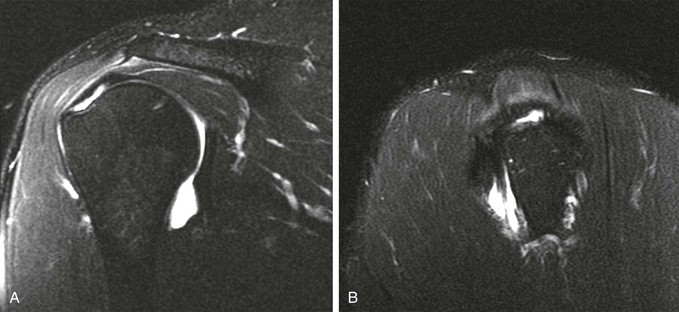

A full-thickness tear of the rotator cuff tendon is defined as a tear that extends through the complete thickness of the tendon from superior to inferior. This tear allows communication between the joint space and the subacromial-subdeltoid bursa. MRI criteria for establishing the diagnosis of a full-thickness tear include high (fluid) signal completely traversing the tendon from superior to inferior on T2-weighted images, a gap or absence of the tendon, and retraction of the musculotendinous junction (Fig. 44-21).

Although conventional MRI is established as the imaging modality of choice in the evaluation of shoulder impingement syndrome, MRA is accepted as the method of choice for the evaluation of glenohumeral instability.22,23 Many of the lesions associated with instability are subtle and may undergo partial healing. This situation, coupled with the fact that the normal anatomic structures of the shoulder lie in close proximity, can make the diagnosis of these lesions difficult even with high-quality conventional MRI.58-62 MRA, on the other hand, is performed by distending the joint with fluid (saline solution or dilute gadolinium), which more accurately depicts subtle labral tears, cartilage and ligamentous abnormalities, and partial-thickness tears of the undersurface of the rotator cuff. The standard injection technique for MRA of the shoulder is described in previous sections. About 12 to 14 mL of gadolinium diluted 1 : 200 with normal saline solution or 1% lidocaine is injected. Imaging protocols vary, but a standard set of imaging sequences typically includes T1-weighted images with frequency-selective fat saturation in the axial, oblique sagittal, and oblique coronal planes. The T1-weighted images have a high signal/noise ratio, resulting in the anatomic detail that is critical in detecting the subtle lesions associated with glenohumeral instability. A T2-weighted sequence performed in the oblique coronal plane is the most important sequence for depicting rotator cuff abnormalities. A T2-weighted sequence may also be helpful in detecting other pathologic processes, such as a paralabral cyst or bone marrow edema (Fig. 44-7, A and B). The ABER view may be added to the standard imaging protocol for any patient thought to have an anterior labral pathologic process.54